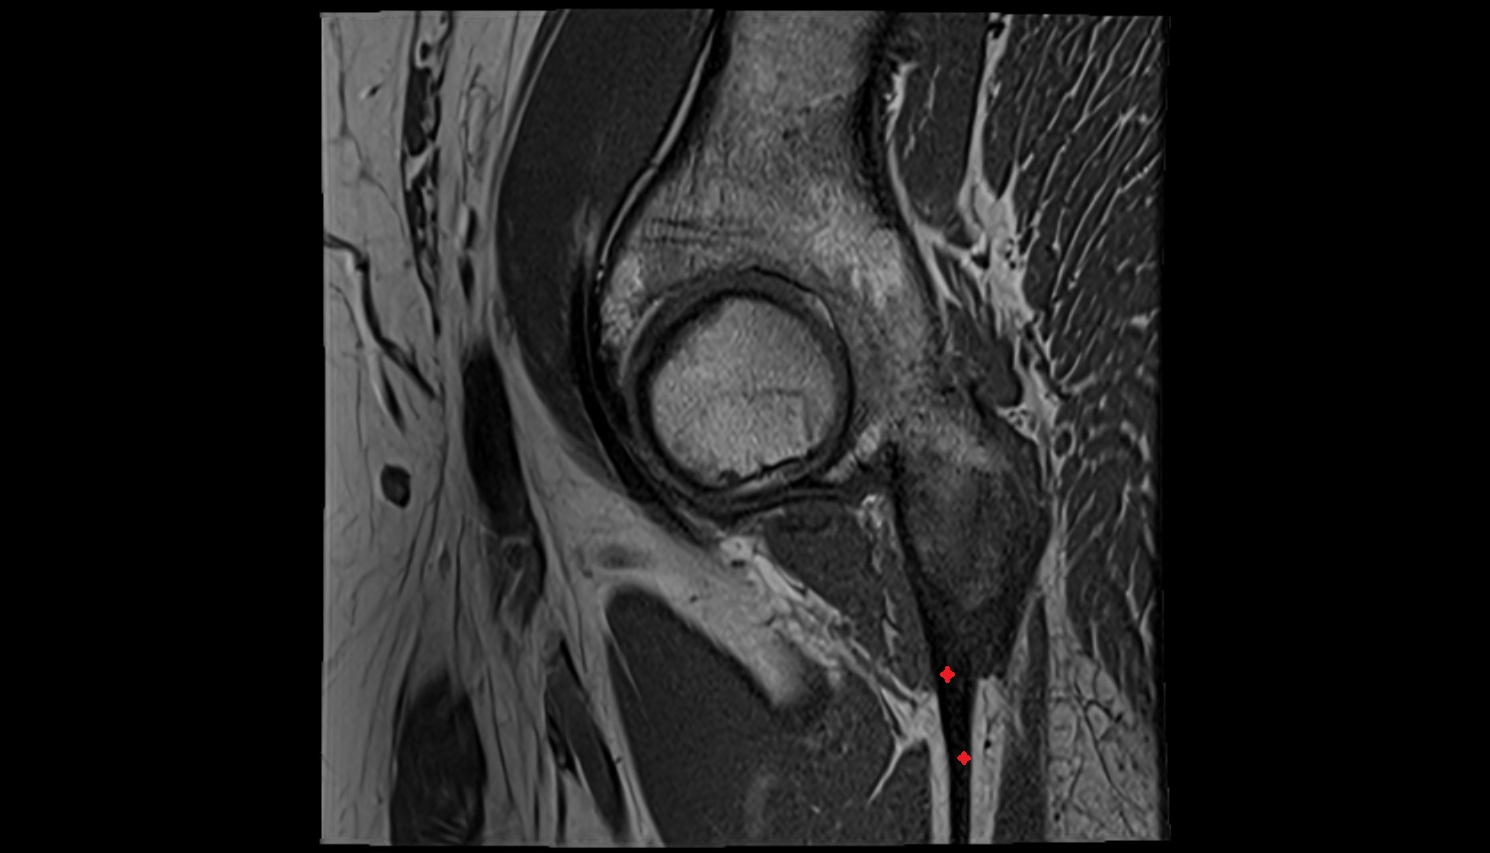

- Knee Joint